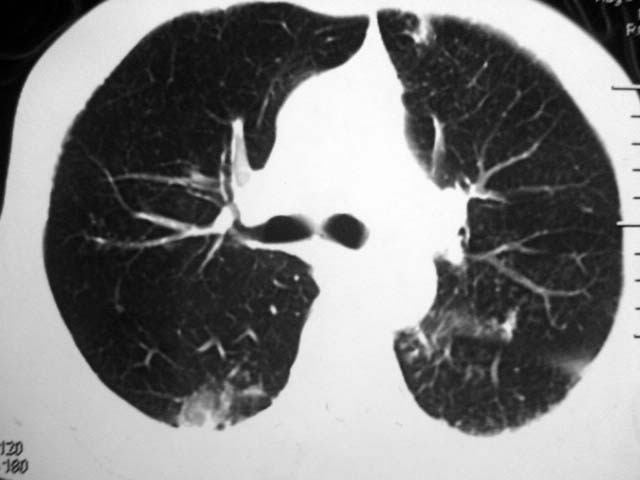

男,52岁,发热2月,糖尿病史。

抗结核治疗irpz方案,血糖未治疗,空腹15.9左右。症状无好转,左胸痛。

复查ct

2、双肺见多发片状及结节状高密度影,大多数病灶中心均见“空泡征”。

3、纵隔内淋巴结肿大。

结果:两肺继发性肺结核并曲霉菌感染。